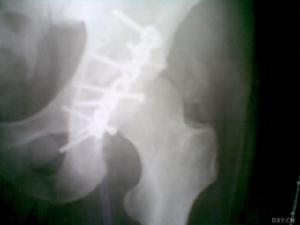

顱骨骨髓炎--X線拍片2.局限性頭痛和壓痛:在病程2周左右骨髓炎化膿穿破外板形成骨膜下膿腫而出現波動感;穿破內板並發顱內併發症出現昏迷、癲癇、失語、偏癱等表現。

3.頭部X線拍片:早期可無變化,亞急性與慢性期顯示骨質破壞,死骨形成或增生硬化等骨質徵象。

顱骨骨髓炎早期容易忽略,X線照片也只有在感染2~3周之後始能看到明顯的脫鈣和破壞徵象。慢性骨髓炎此X線較易顯示蟲蝕狀密度不均的骨質破壞區,其間有時可見密度甚高的片狀死骨影像,為時過久的慢性顱骨骨髓炎,尚可在破壞區周圍出現骨質硬化和增生,故X線平片可以確診。